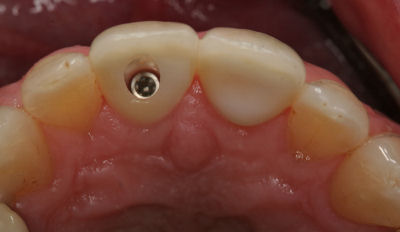

It is important that you understand that implant restorations consist of two parts, the titanium implant and the implant crown. Research has demonstrated that dental implants may remain integrated with bone in excess of 25 years and many implants will remain integrated for life. The limiting factor for the survival of implant restorations is usually the implant crown. Maintenance issues that may occur with the implant crown include fracture of porcelain or the framework, screw loosening, screw fracture and loss of the filling within the screw access hole.

Usually problems involving the implant crown can be repaired or replaced relatively easily, provided the implant remains integrated in bone. It is difficult to give you an accurate estimate of exactly how long the crown will last, as this is dependent on many factors within and beyond our control. However what we do know is that most early complications with materials tend to occur within the first year of service and provided the implant crown is maintained in a meticulous manner with routine checks, you should get many years of satisfactory service.